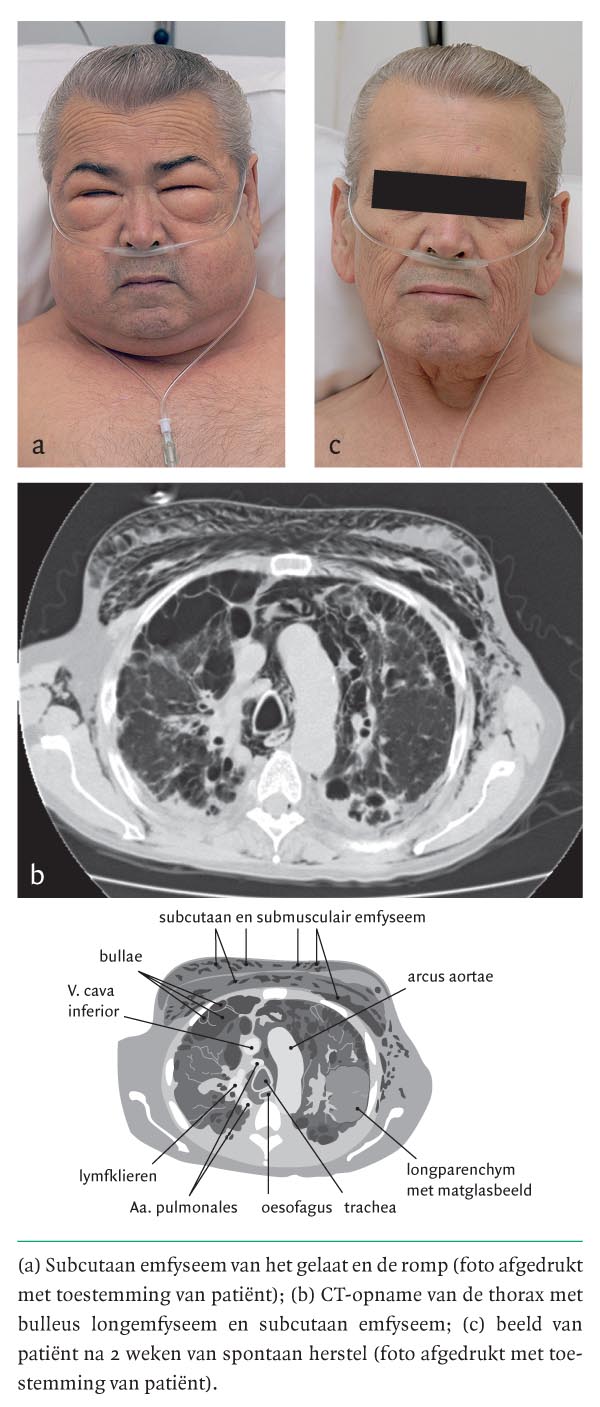

Een 65-jarige man presenteerde zich met dyspneu en een toename van de gelaatsomvang. Zijn voorgeschiedenis vermeldde COPD, ernstig bulleus emfyseem en recidiverende pneumothorax, waarvoor beiderzijds chemische pleurodese had plaatsgevonden. Lichamelijk onderzoek toonde subcutaan emfyseem van gelaat (figuur a) en romp. Patiënt was hemodynamisch stabiel met een perifere zuurstofsaturatie van 95 tijdens toediening van 4 l O2/min. De ademweg was niet bedreigd. Bij auscultatie werd een piepend verlengd exspirium over alle longvelden gehoord. Een thoraxröntgenfoto toonde subcutaan emfyseem zonder pneumothorax; bij CT werd het bekende bulleuze emfyseem gezien (zie figuur b). Er was mogelijk een…